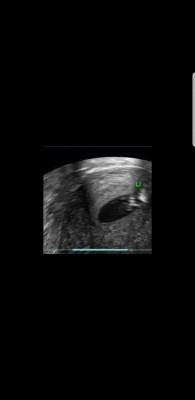

Meine KiWu hat mir vor dem Transfer eine Hydrosonographie empfohlen, diese heute morgen getätigt mit dem Ergebnis: Da ist etwas, was nicht sein sollte. Mehr würde ich aber erst erfahren bei der Spezialistin, diese hätte aber erst Mitte Januar Zeit.

Bilder angehängt